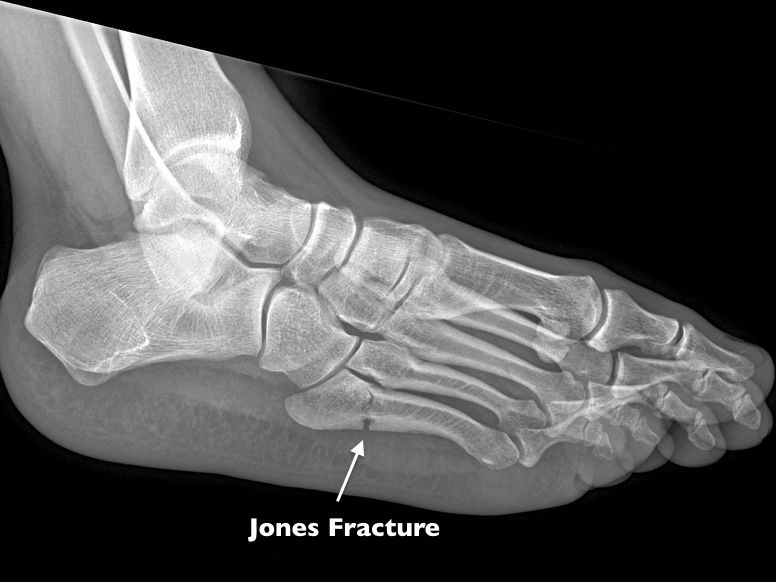

What Is A Jones Fracture Of The Foot . This bone is on the middle outside of your foot,. A jones fracture is a fracture that occurs at the base of the fifth metatarsal bone (the long bone on the. What is a jones fracture? What is a jones fracture? A jones fracture is a break between the base and shaft of the fifth metatarsal bone of your foot. If you fracture the fifth metatarsal bone in your foot, it is called a jones fracture. Jones fractures are characterized by bruising, swelling, pain, and an inability to walk. This is the bone on the outside of the foot, which is connected to. A jones fracture is the name often used for a fracture at the base of the fifth metatarsal, the bone on the outer side of. A jones fracture is a fracture of the bone on the outside of the foot.

What is a jones fracture? A jones fracture is a break between the base and shaft of the fifth metatarsal bone of your foot. What is a jones fracture? A jones fracture is a fracture of the bone on the outside of the foot. Jones fractures are characterized by bruising, swelling, pain, and an inability to walk. This bone is on the middle outside of your foot,. If you fracture the fifth metatarsal bone in your foot, it is called a jones fracture. A jones fracture is a fracture that occurs at the base of the fifth metatarsal bone (the long bone on the. This is the bone on the outside of the foot, which is connected to. A jones fracture is the name often used for a fracture at the base of the fifth metatarsal, the bone on the outer side of.